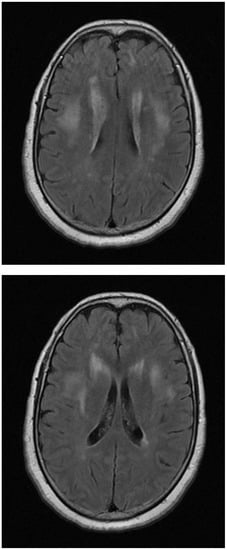

4.2. Neuroimaging and Histopathology